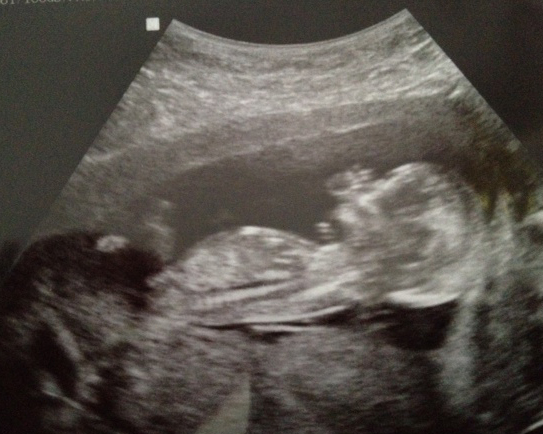

Potty shot at 16w0d

Attachment 2765